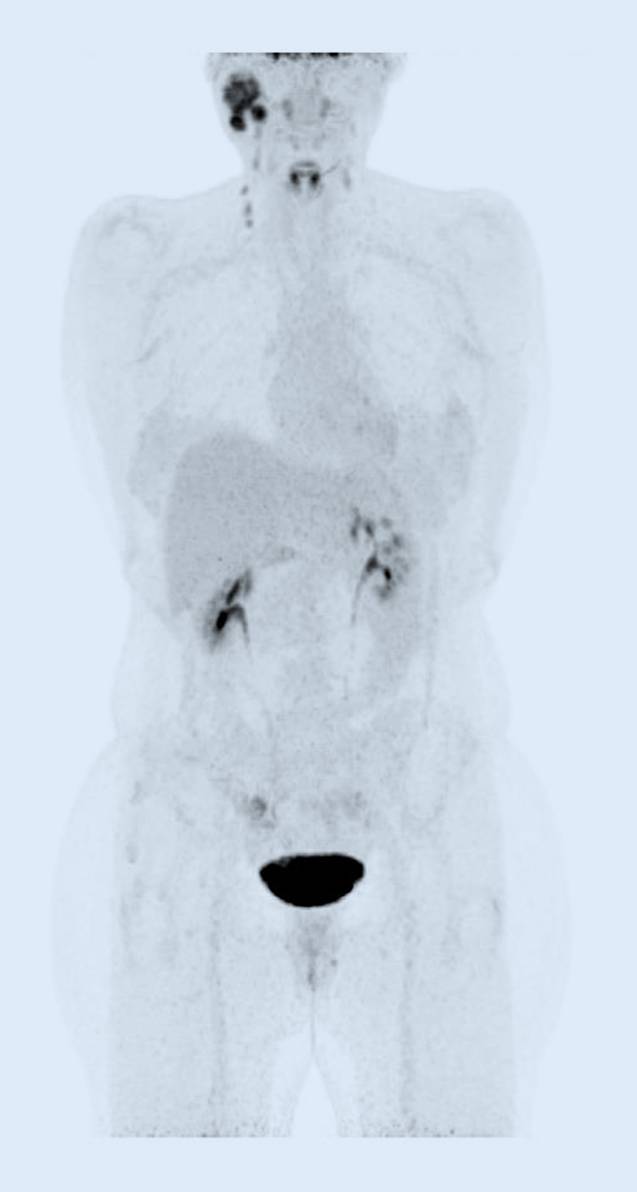

18-Fluordesoxyglucose-Positronenemissionstomographie-Fusions-Computertomographie (18-FDG-PET-Fusions-CT) und Ganzkörper-18-FDG-PET vom Juni 2023 zeigen den Primärtumor und die Hals-Lymphknotenmetastasen, jedoch keine Fernmetastasierung (Abb. 1 und 2).

Abb. 2

Ganzkörper-18-FDG-PET mit Primärtumor und Halslymphknotenmetastasen, ohne Nachweis von Fernmetastasen vom Juni 2023